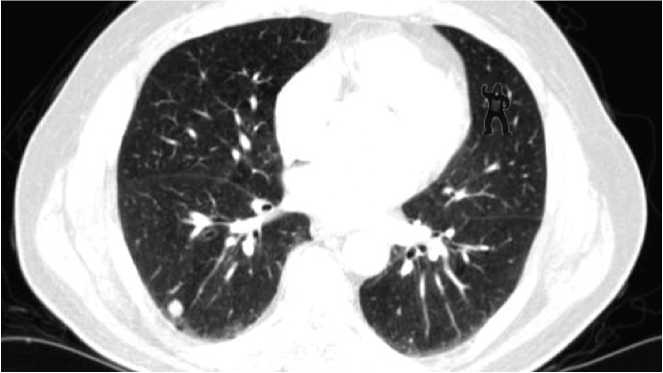

Слепота невнимания — это не просто следствие первого наблюдения незнакомой сцены (например, баскетбольного матча с участием гориллы). Дефект восприятия также распространяется на людей, которые проводили бесчисленные часы, наблюдая одну и ту же сцену снова и снова. Например, было проведено исследование с участием радиологов, которые анализируют компьютерную томографию при диагностике рака легких [132]. Радиологам показали пять снимков компьютерной томографии с опухолевыми узлами и попросили описать их. Небольшое изображение гориллы было помещено в верхний правый квадрант пятого снимка (рис. 6.4). После того как радиологи закончили писать заключение по пятому снимку, им задали три вопроса:

Иллюстрация к книге — Что такое наука, и как она работает [img_9.jpg]

Рис. 6.4. Слепота невнимания в действии

Из 24 участвовавших в исследовании радиологов только 4 (17 %) заметили гориллу. Исследователи отслеживали движения глаз рентгенологов, поэтому они могли опровергнуть предположение о том, что изображение гориллы просто не попало в поле зрения участников — рентгенологи его видели. Но, несмотря на визуально ощущаемые данные, большинство участников не воспринимали гориллу; они искали паттерны, указывающие на рак, и любые другие детали того, что было прямо перед ними, отсеивались где-то на пути между глазами и их сознанием.